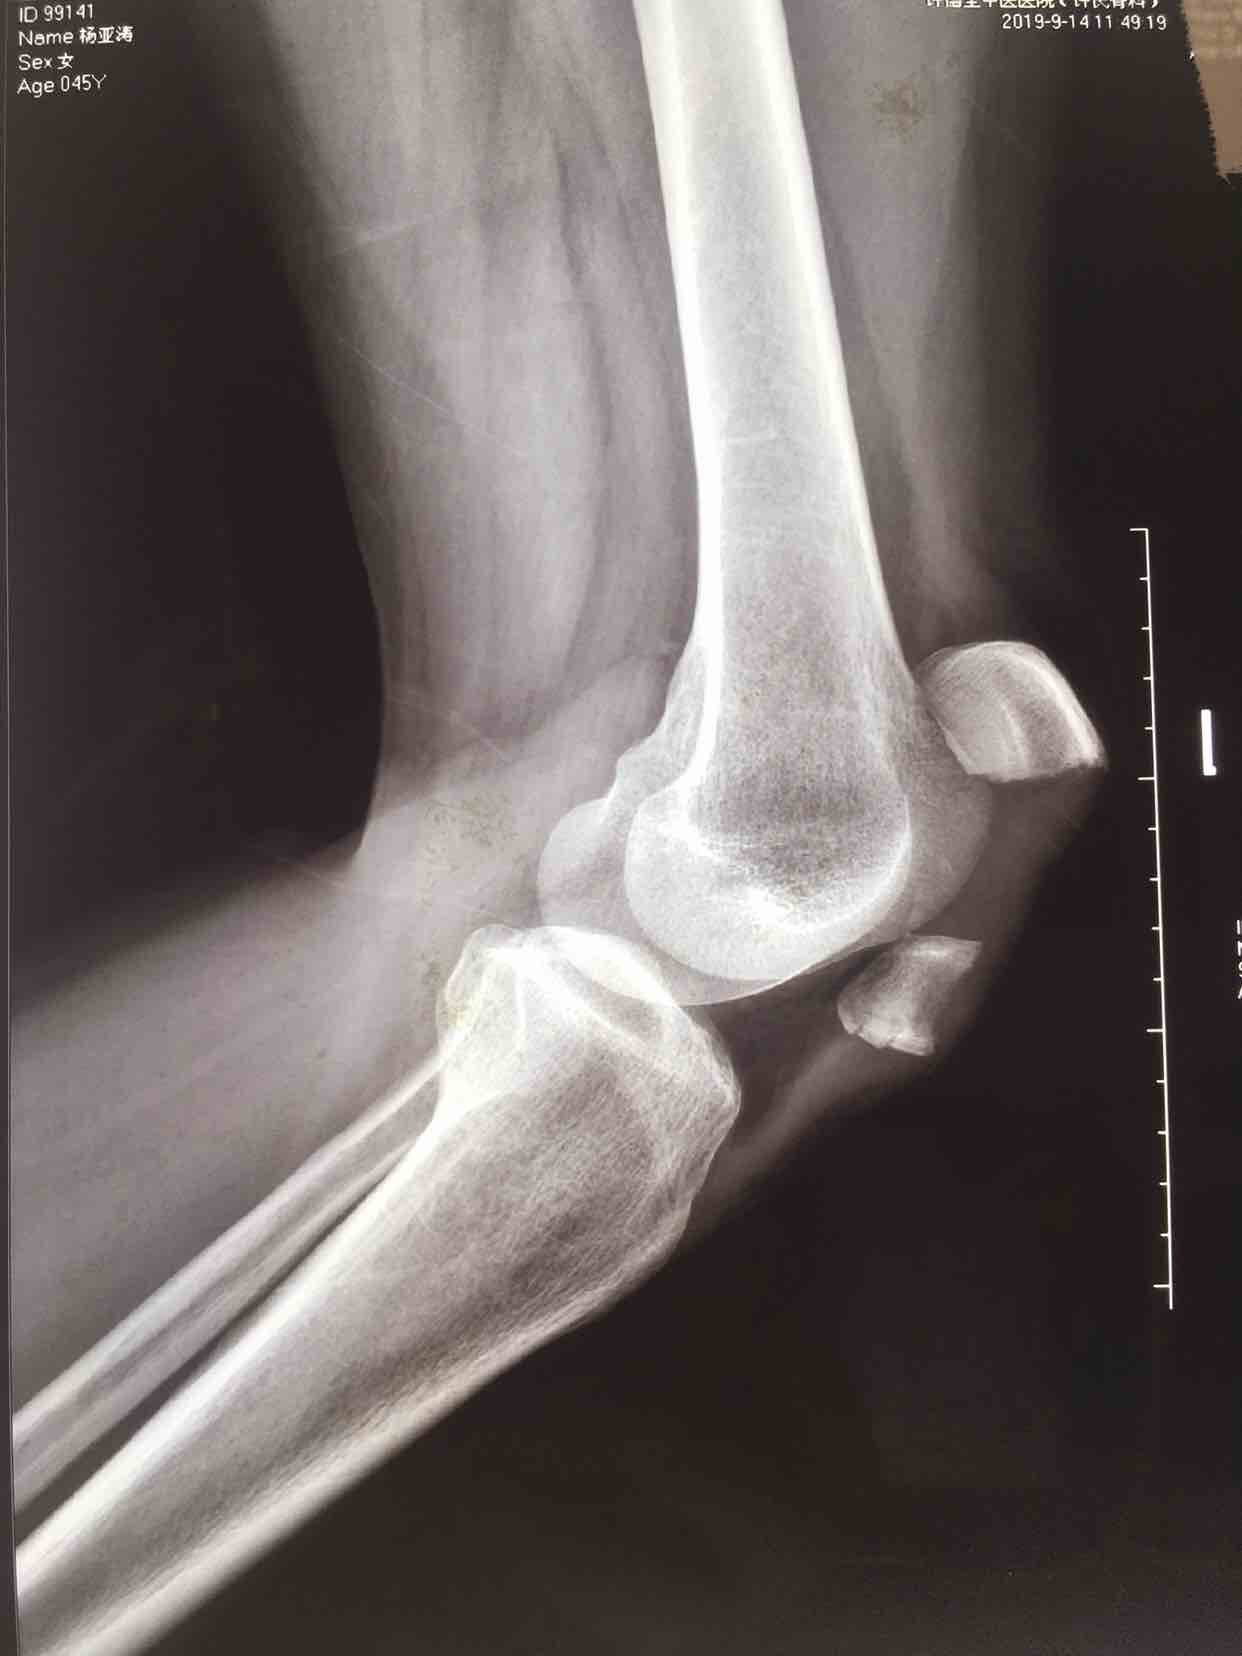

患者:女/四十五岁

摔伤后左膝部肿痛,活动受限1小时。

生命体征平稳,心肺复未见异常。左膝部肿胀明显,局部皮色皮温正常,压痛,可及骨折断端,膝关节伸膝受限,末梢血运感觉正常。

诊断左髌骨粉碎性骨折

在腰麻下行切复内固定术,术后抗炎,消肿等处理。